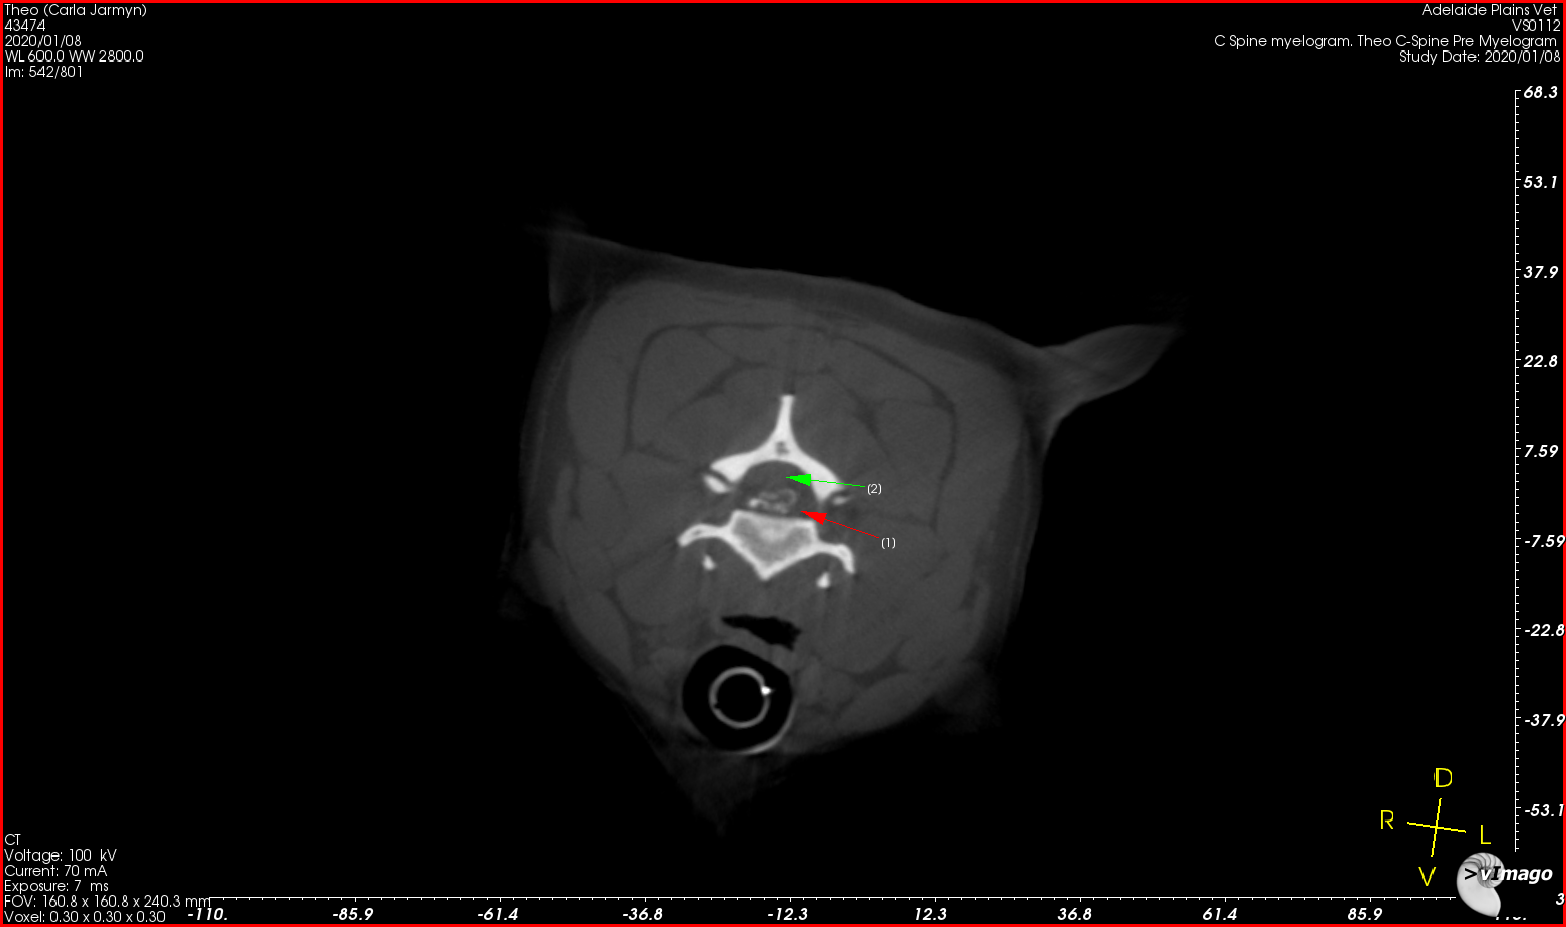

Theo 3

• Theo’s Pain In The Neck